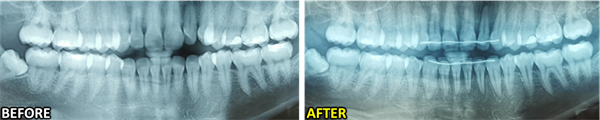

Fixed retainers were placed on both the upper and lower lingual surfaces, canine to canine, following bracket removal (Fig. 4). Panoramic radiographs (Fig. 5) show the corrected position of the teeth with root parallelism in 68 days.

Fig. 5: Before-and-after panoramic radiographs